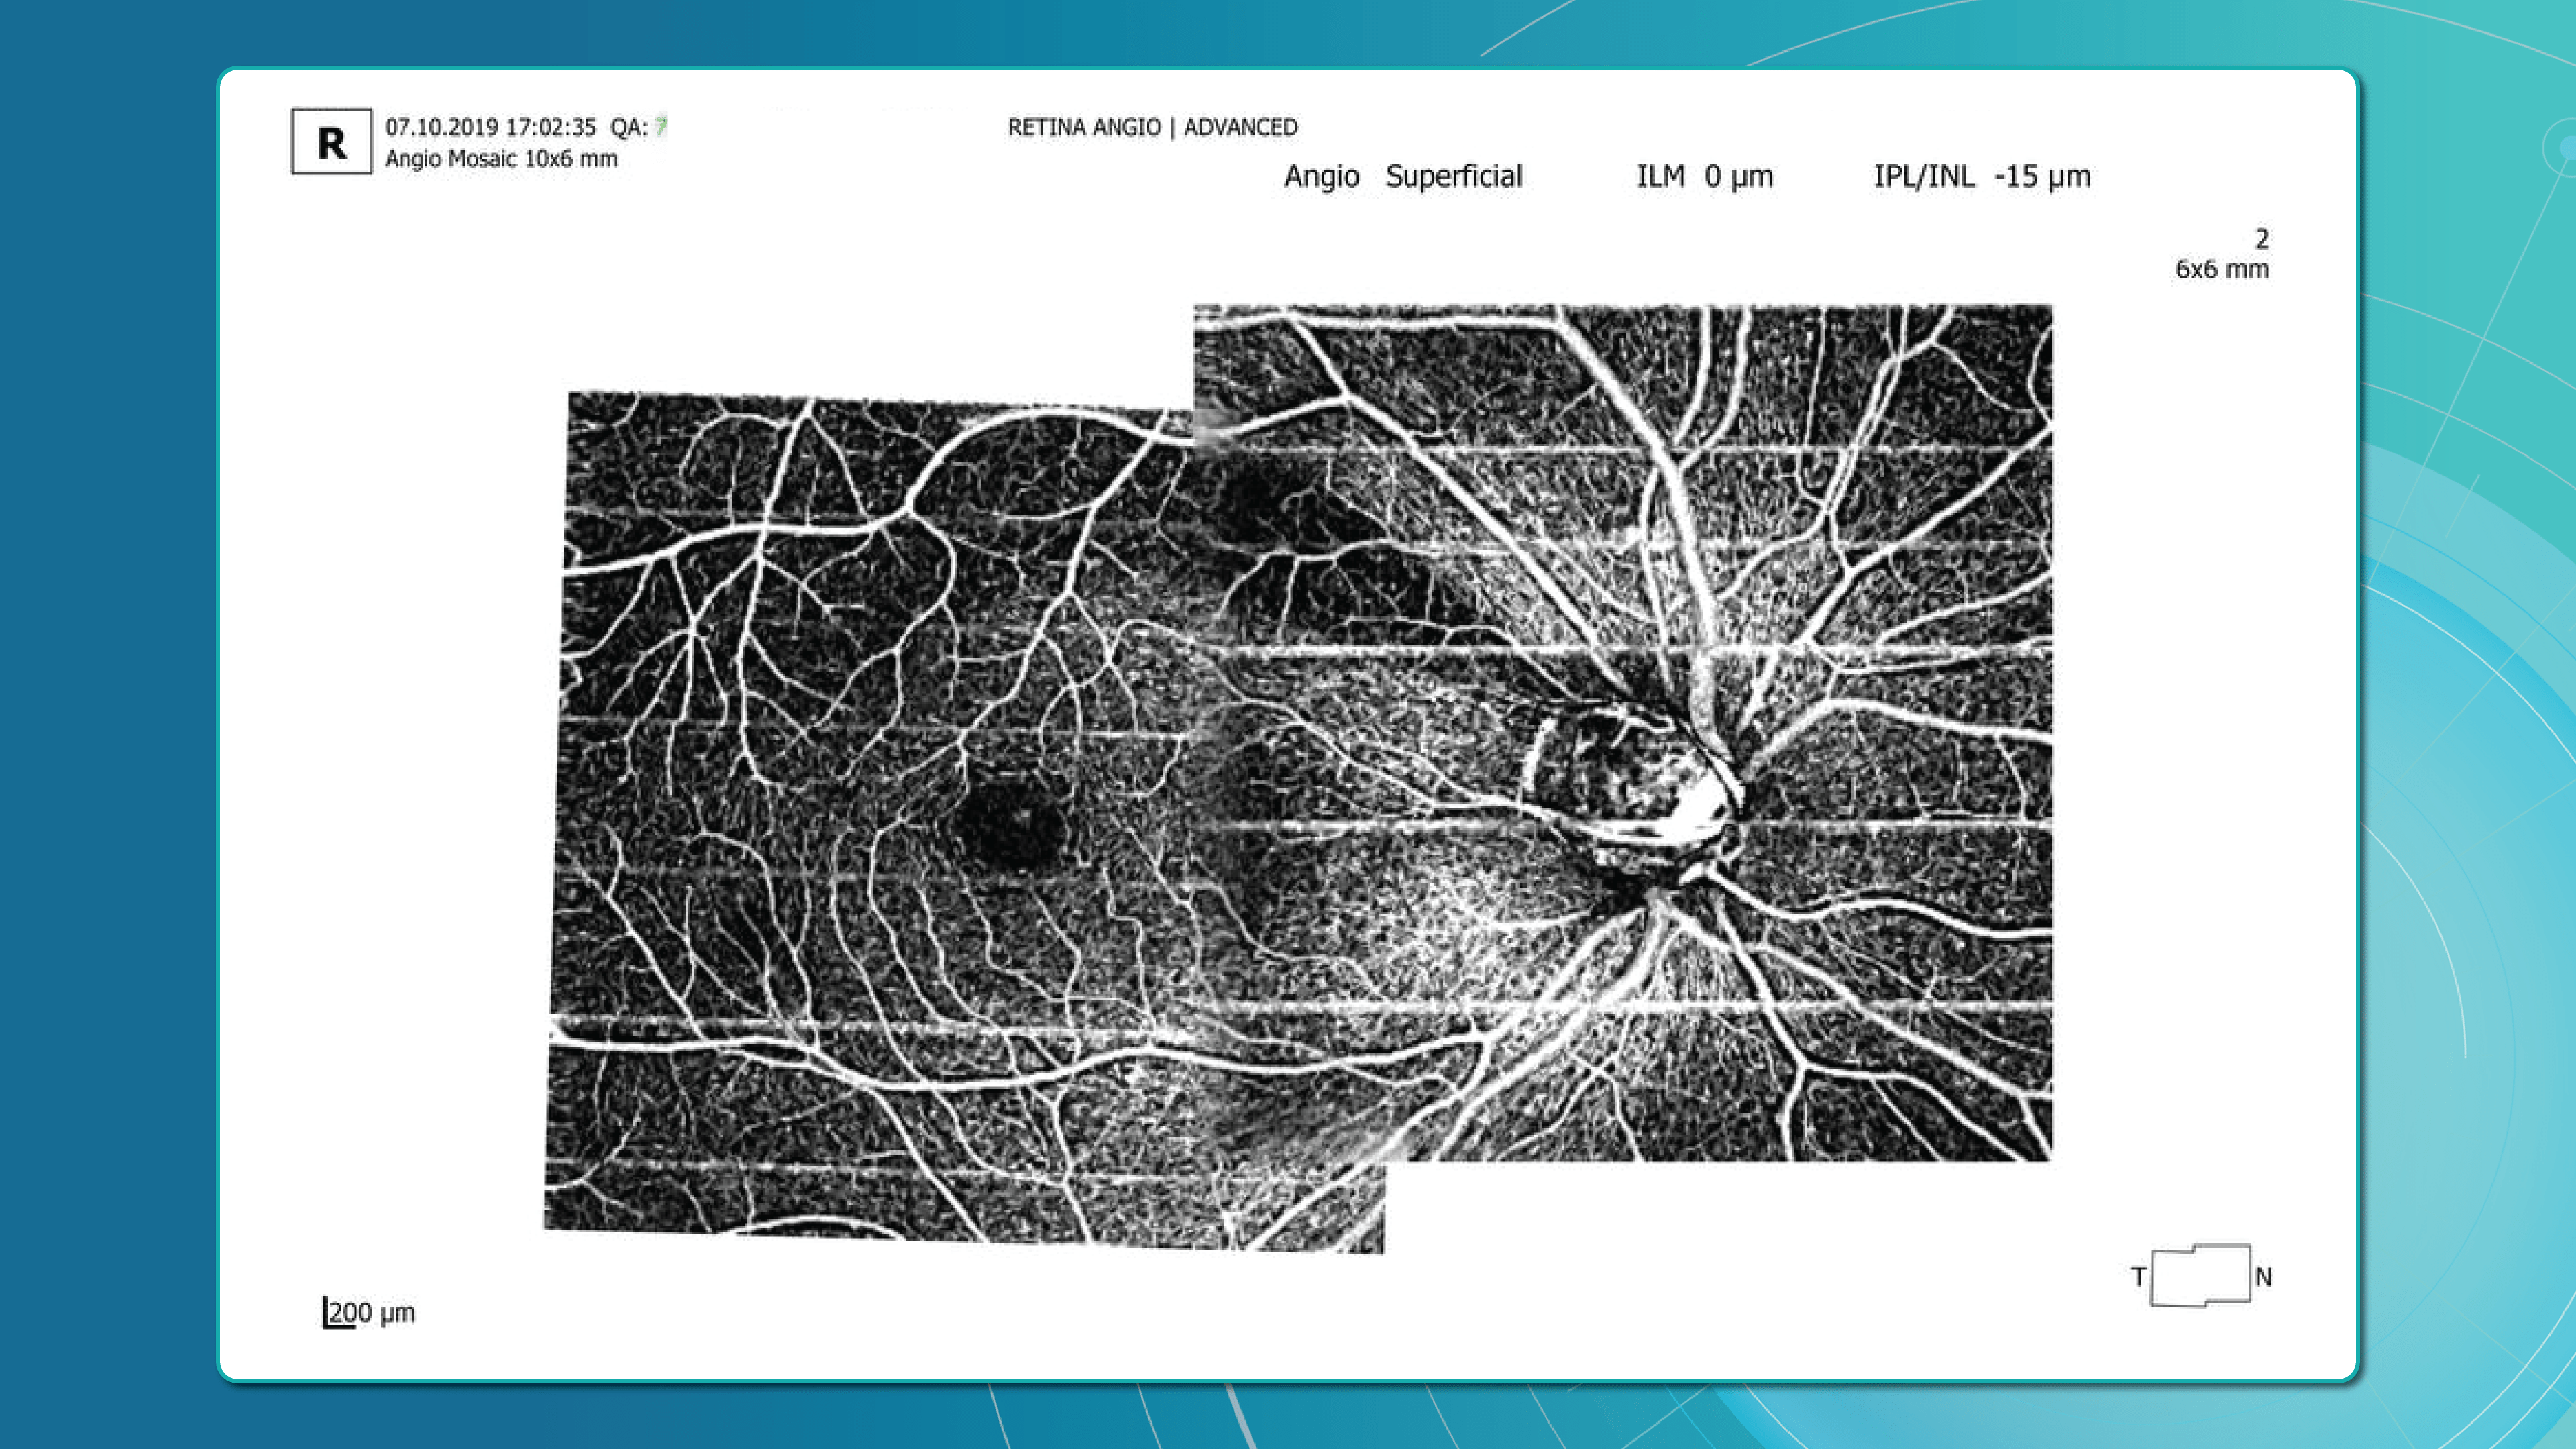

Eye Place, an optometry center in Columbia, also leverages Altris AI, among other cutting-edge technologies. They capture images using the Topcon Maestro2 OCT and use Image Net6 software to export DICOM files to the Altris AI platform.

Beyond AI-powered OCT analysis, Eye Place utilizes state-of-the-art diagnostic tools, such as 3D OCT equipment, to screen for serious conditions, including glaucoma, diabetes, and macular degeneration. Furthermore, they work with AdaptDX Pro, a technology capable of detecting macular degeneration earlier than traditional methods.

Optometry Trends: OCT Angiography

Given that many ocular diseases are associated with vascular abnormalities, the ability to visualize and quantify blood flow in the eye is crucial. Traditionally, fluorescein angiography (FA) and indocyanine green angiography (ICGA) have been used for this purpose, but these procedures require intravenous injection of contrast agents, which is not only time-consuming but may lead to allergic reactions or potentially serious side effects.

OCTA, on the other hand, produces high-resolution, 3D angiograms of the retinal and choroidal vascular networks, taking advantage of the eye’s unique characteristic as the only organ allowing noninvasive, direct observation of its blood vessels’ structure and function. OCTA detects blood flow using intrinsic signals to capture the location of blood vessels. While it has limitations such as insensitivity to leakage and a relatively small field of view, the development of OCTA has the potential to significantly enhance our understanding of the eye’s physiology and pathophysiology, providing depth-resolved angiographic maps of the tissue’s vascular structure down to the capillary level.

OCTA is particularly valuable in clinical settings where pathologies like diabetic retinopathy, age-related macular degeneration, retinal vein occlusions, and macular telangiectasia are frequently encountered. These conditions often alter blood flow or the blood vessels themselves in the retina, making imaging these vessels essential for diagnosis and management.